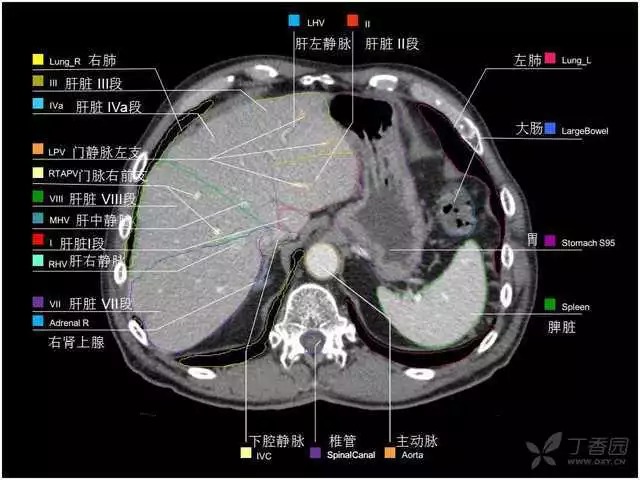

腹部肝脏高清CT断层的图谱

全腹部高清CT图谱,淋巴结彩色图谱,血管解剖图谱大汇总!

超声肝脏分叶及分段

肝脏分段和基本解剖学标志